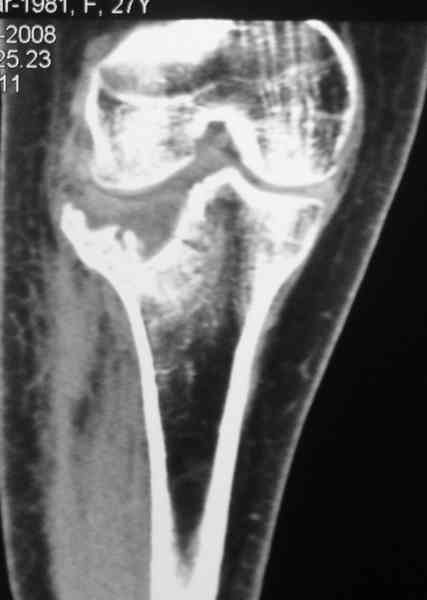

Уважаемый Абдурашид. Если нет противопоказаний , то из оперативных способов, я бы рекомендовал следующие: Полное замещение наружного мыщелка аллотрансплантатом либо открытая репозиция с элевацией и замещение дефекта ауто или аллокостью. В Ваших условиях , я бы рекомендовал второй способ. Во-время элевации необходимо разъединить фрагменты со стороны сустава ( надсечь скальпелем по линиям перелома, а затем тонким остеотомом их разъединить. При помощи долота произвести неполную остеотомию ( захватите не менее 1,5 - 2 см губчатой кости и поднять фрагменты, визуально отрепонировать и фиксировать 2-3 спицами. Дефект заместить костным ауто или аллатрансплантатом. Окончательная стабилизация пластиной ( лучше с угловой стабильностью, либо АВФ - позволит спокойно устранить угловую деформацию.

Недавно поступила больная через 1,5- 2 месяца.